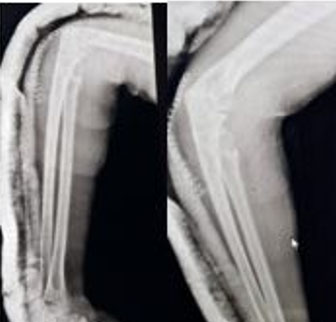

On anteroposterior and lateral view X-ray, there was a large bony excrescence originating from the radial neck and was extended toward the elbow joint. The lesion appeared to be mostly hyperdense, containing hypodense. No signs of fracture or dislocation could be seen (Figure 2).

Figure 2: X-ray of right elbow, AP, and lateral views.